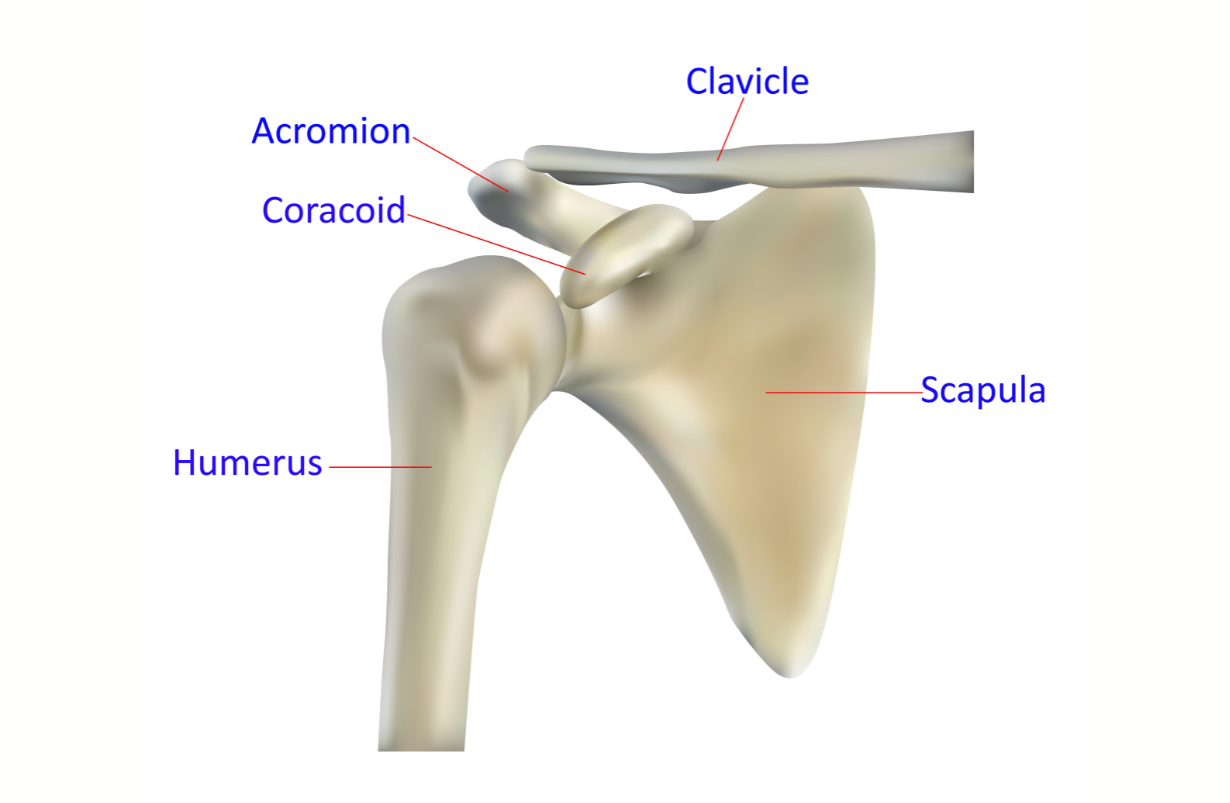

Arthritis Shoulder

Erosion of cartilage and dysfunctional reshaping of the bones forming the shoulder joint, the humerus and the glenoid fossa, part of the scapula or shoulder blade.

Shoulder Impingement

Non-physiological and painful contact between the humerus (arm bone) and the acromion (highest and most lateral part of the scapula or shoulder blade) that restricts abduction and flexion of the arm. It is generally due to extra bone formation on the lower surface of the acromion which intersects the humerus at 140 -150 degrees, instead of allowing it to abduct and flex closer to 170 - 180 degrees.